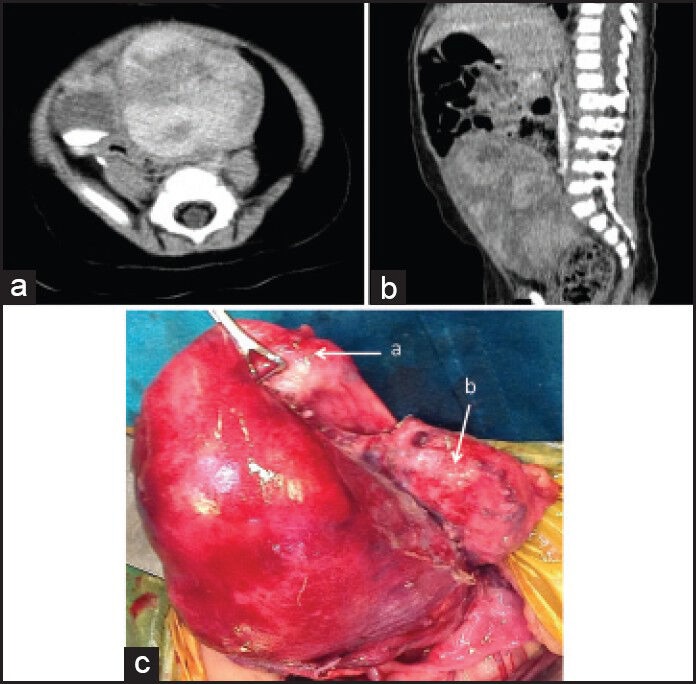

The case we present here is a 9-month-old female child, presented to us with the complaints of straining at micturition and defecation since the age of 5 months. The patient was diagnosed with benign partial epilepsy of infancy and was under treatment for the same. No other comorbidities were present. On examination, the patient had multiple Café au lait spots over her body (more than 5 in number). However, there were no other features to suggest neurofibromatosis, like, family history, Lisch nodules, axillary or inguinal freckling and osseous lesions. Abdominal examination revealed an abdominopelvic mass, in the midline, extending superiorly to just above the umbilicus. The mass was firm to hard in consistency and mobile. The mass was also felt on per-rectal examination. A contrast enhanced computed tomography (CECT) scan of the abdomen and pelvis confirmed the clinical findings of an abdominopelvic mass of about 9.8 cm × 6 cm × 5 cm extending from the level of acetabulum in the pelvis, to the level of L3 vertebra [Figure 1]. The mass was isodense to hypodense on a plain scan with heterogenous enhancement on post-contrast scan. The urinary bladder was pushed to the right side due to mass effect but planes were maintained. There was mild left-sided hydronephrosis with the distal left ureter not visualized. The uterus and adnexa were not visualized separately. A percutaneous biopsy done from the mass revealed ERMS. The metastatic work-up, including a bone scan, CECT thorax and bone marrow examination, was normal.

| Figure 1:Contrast enhanced computed tomography scan showing the heterogenously enhancing mass arising from pelvis, with contrast in urinary bladder (a and b). Intra-operatively (c), the mass seen arising from the broad ligament, the uterus (a) and urinary bladder (b) separated

The patient received neoadjuvant chemotherapy (NACT), as per intergroup rhabdomyosarcoma study group (IRS) IV protocol (vincristine, actinomycin and cyclophosphamide). The post NACT CECT scan showed a stable disease. An exploratory laparotomy performed revealed a lobulated mass of 10 cm × 5 cm × 5 cm [Figure 1]. The mass had a pedicle and was seen to be arising from the left broad ligament. The uterus and adnexa were separate from the mass, pushed to the right side. The mass was densely adhered to the urinary bladder but could be separated by dissection. The ureters on both sides were separate from the mass. The mass was excised in-toto preserving the uterus and the adnexae. The post-operative course of the patient was uneventful. The final histopathology revealed an ERMS with cut margin negative for tumor. The Immunohistochemistry studies were positive for desmin and myosin [Figure 2]. As per the TNM and IRS staging, our patient was staged as Stage I, Group III, with embryonal histology and thus classified as low risk subgroup.[6] The patient was treated with adjuvant chemotherapy as per IRS IV protocol.